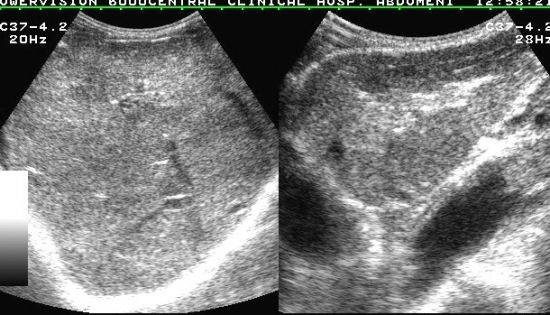

На начальных стадиях у больного появляется тошнота и слабовыраженная боль в районе правого подреберья, но обычно на это мало кто обращает внимание. Чаще диффузные изменения уже обнаруживаются при прохождении УЗИ. Дополнительно может потребоваться проведение КТ, рентгенографии, анализа крови

На УЗИ специалист также может выявить липоматоз. Патологический процесс может быть связан с генетическими факторами, а также возрастными изменениями. Орган уменьшается в размерах и замещается жировыми клетками. К сожалению, липоматоз вызывает необратимые процессы. Заплывший жиром орган сдавливает паренхимы, что и вызывает сильную боль.

Пациенты могут подумать, что диффузные изменения поджелудочной железы — это панкреатит. А вот и нет. Сами по себе диффузные изменения поджелудочной железы ни о чём не говорят. Для того, чтобы утверждать, что эти изменения возникли из-за панкреатита, необходимо наличие симптомов панкреатита, а также изменения в лабораторных анализах: повышение амилазы панкреатической в крови, повышение диастазы мочи, снижение амилазы кала, наличие нейтрального жира и/или жирных кислот в большом количестве в копрограмме.

Выявление любой степени фиброза говорит о том, что печёночные ткани подверглись изменениям. Как уже говорилось, эти изменения могут указывать как на начальные стадии какого-либо патологического процесса, так и на течение тяжёлого заболевания. Поэтому нужно, помимо УЗИ, проводить дополнительные диагностические мероприятия (например, лабораторные и гистологические исследования), позволяющие определить степень фиброза и поражения печени.

Тут даже не один случай, а множество случаев, когда перепуганные результатами ультразвукового исследования пациенты думали, что у них панкреатит или цирроз. Эти изменения должны оцениваться в совокупности с жалобами и результатами анализов.